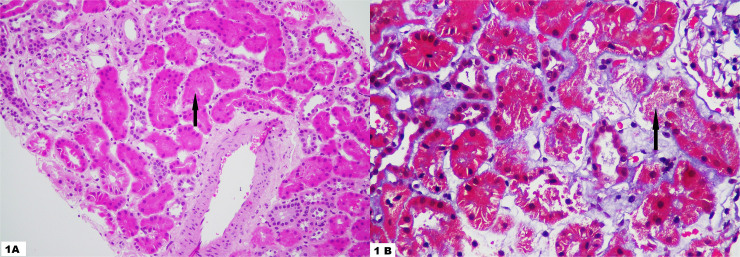

Hashimoto's thyroiditis manifesting as hypothyroidism has been implicated in glomerular disorders due to autoantibody formation. Here we present the case of a 26-year-old male without any comorbidities presenting with easy fatiguability and weight gain for 2 months. He was found to have a creatinine of 2.1 mg/dL with a history of rhinitis treated with anti-histaminic three days prior to the hospital visit. He had symptoms of intermittent myalgia for the past two weeks. On laboratory evaluation, he was found to have raised CPK, elevated TSH, low normal T4, and positive anti-TPO and anti-Tg antibodies. Neck ultrasound revealed linear echogenic septations in the thyroid gland. Renal biopsy revealed acute tubular injury. Appropriate thyroxine supplementation was started and his creatinine decreased to 1.2 mg/dL after 1 month. It is important that clinicians should be aware of this rare kidney presentation in Hashimoto's thyroiditis.